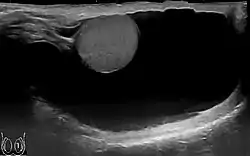

Scrotal ultrasound of a 10 cm large hydrocele, with anechoic (dark) fluid surrounding the testicle.

Scrotal ultrasound of a 10 cm large hydrocele, with anechoic (dark) fluid surrounding the testicle. Communicating hydrocele, caused by the failure of the processus vaginalis closure.